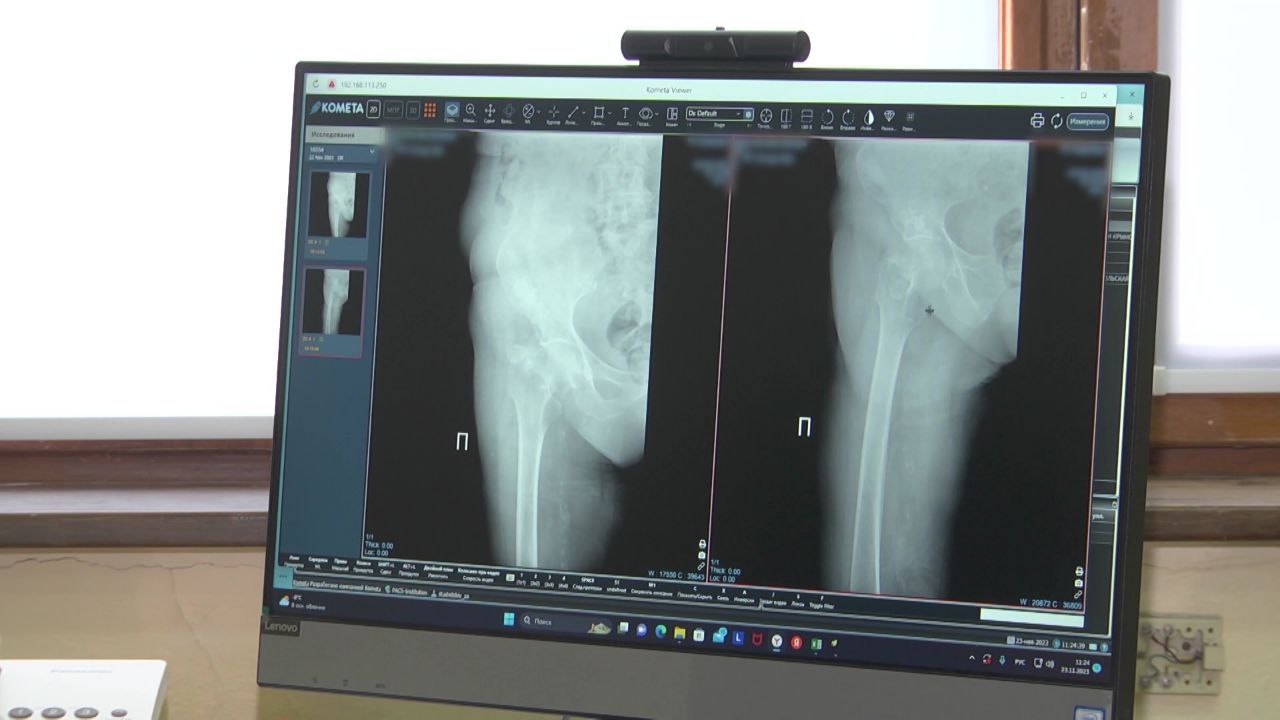

С начала года в Белгородской области провели более 2,5 тысяч операций по эндопротезированию

Врачи помогли людям избавиться от болезней коленных и тазобедренных суставов.